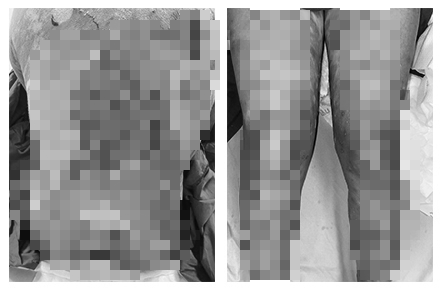

Plus d'une semaine avant son admission à l'hôpital, la patiente présentait des plaques rouges et prurigineuses sur les deux paumes. Les lésions ont ensuite évolué vers des cloques, des cloques superficielles, facilement perforantes, laissant des érosions. Des lésions similaires sont apparues sur les deux plantes des pieds, le tronc, les bras et les jambes, ainsi qu'une nécrose cutanée généralisée, provoquant de fortes douleurs.

Les patients victimes d'une intoxication médicamenteuse présentent des ulcères cutanés et des lésions rouges. Photo : fournie par le médecin.

La patiente a déclaré avoir suivi des traitements de médecine traditionnelle chinoise pendant environ un mois pour améliorer sa santé. Après près de trois semaines de traitement, la maladie a commencé à se développer.

Le patient a reçu un diagnostic de nécrolyse épidermique toxique (syndrome de Lyell) et a bénéficié d'un traitement intensif au sein du service, utilisant des médicaments spécifiques et des soins de soutien. Après 10 jours de traitement, les lésions cutanées étaient sèches, l'épiderme a commencé à se régénérer et il n'y avait plus de nouvelles cloques.

Le deuxième cas concerne une patiente de 55 ans, hospitalisée pour des plaques nécrotiques foncées et des érosions cutanées. Initialement, la patiente présentait des plaques rouge foncé et un gonflement autour des lèvres, puis les plaques rouges se sont rapidement propagées aux mains, aux pieds et au tronc, formant d'autres cloques et vésicules.

Le patient a été hospitalisé avec une forte fièvre, un faible taux de globules blancs et une augmentation des enzymes hépatiques, accompagnés de nombreuses zones de peau rouge foncé, reliées entre elles en plaques, cloques et nécrose cutanée diffuse.

Deux mois avant de tomber malade, cette femme a pris des plantes médicinales pour traiter les douleurs articulaires, puis a pris des plantes médicinales (médicaments bouillis) pour traiter la gastrite pendant trois semaines.

Le patient a reçu un diagnostic de nécrolyse épidermique toxique (syndrome de Lyell) et a bénéficié d'un traitement intensif au sein du service, à l'aide de médicaments spécifiques. Après 7 jours de traitement, les lésions cutanées ont séché, l'épiderme a commencé à se régénérer et aucune nouvelle vésicule n'est apparue.